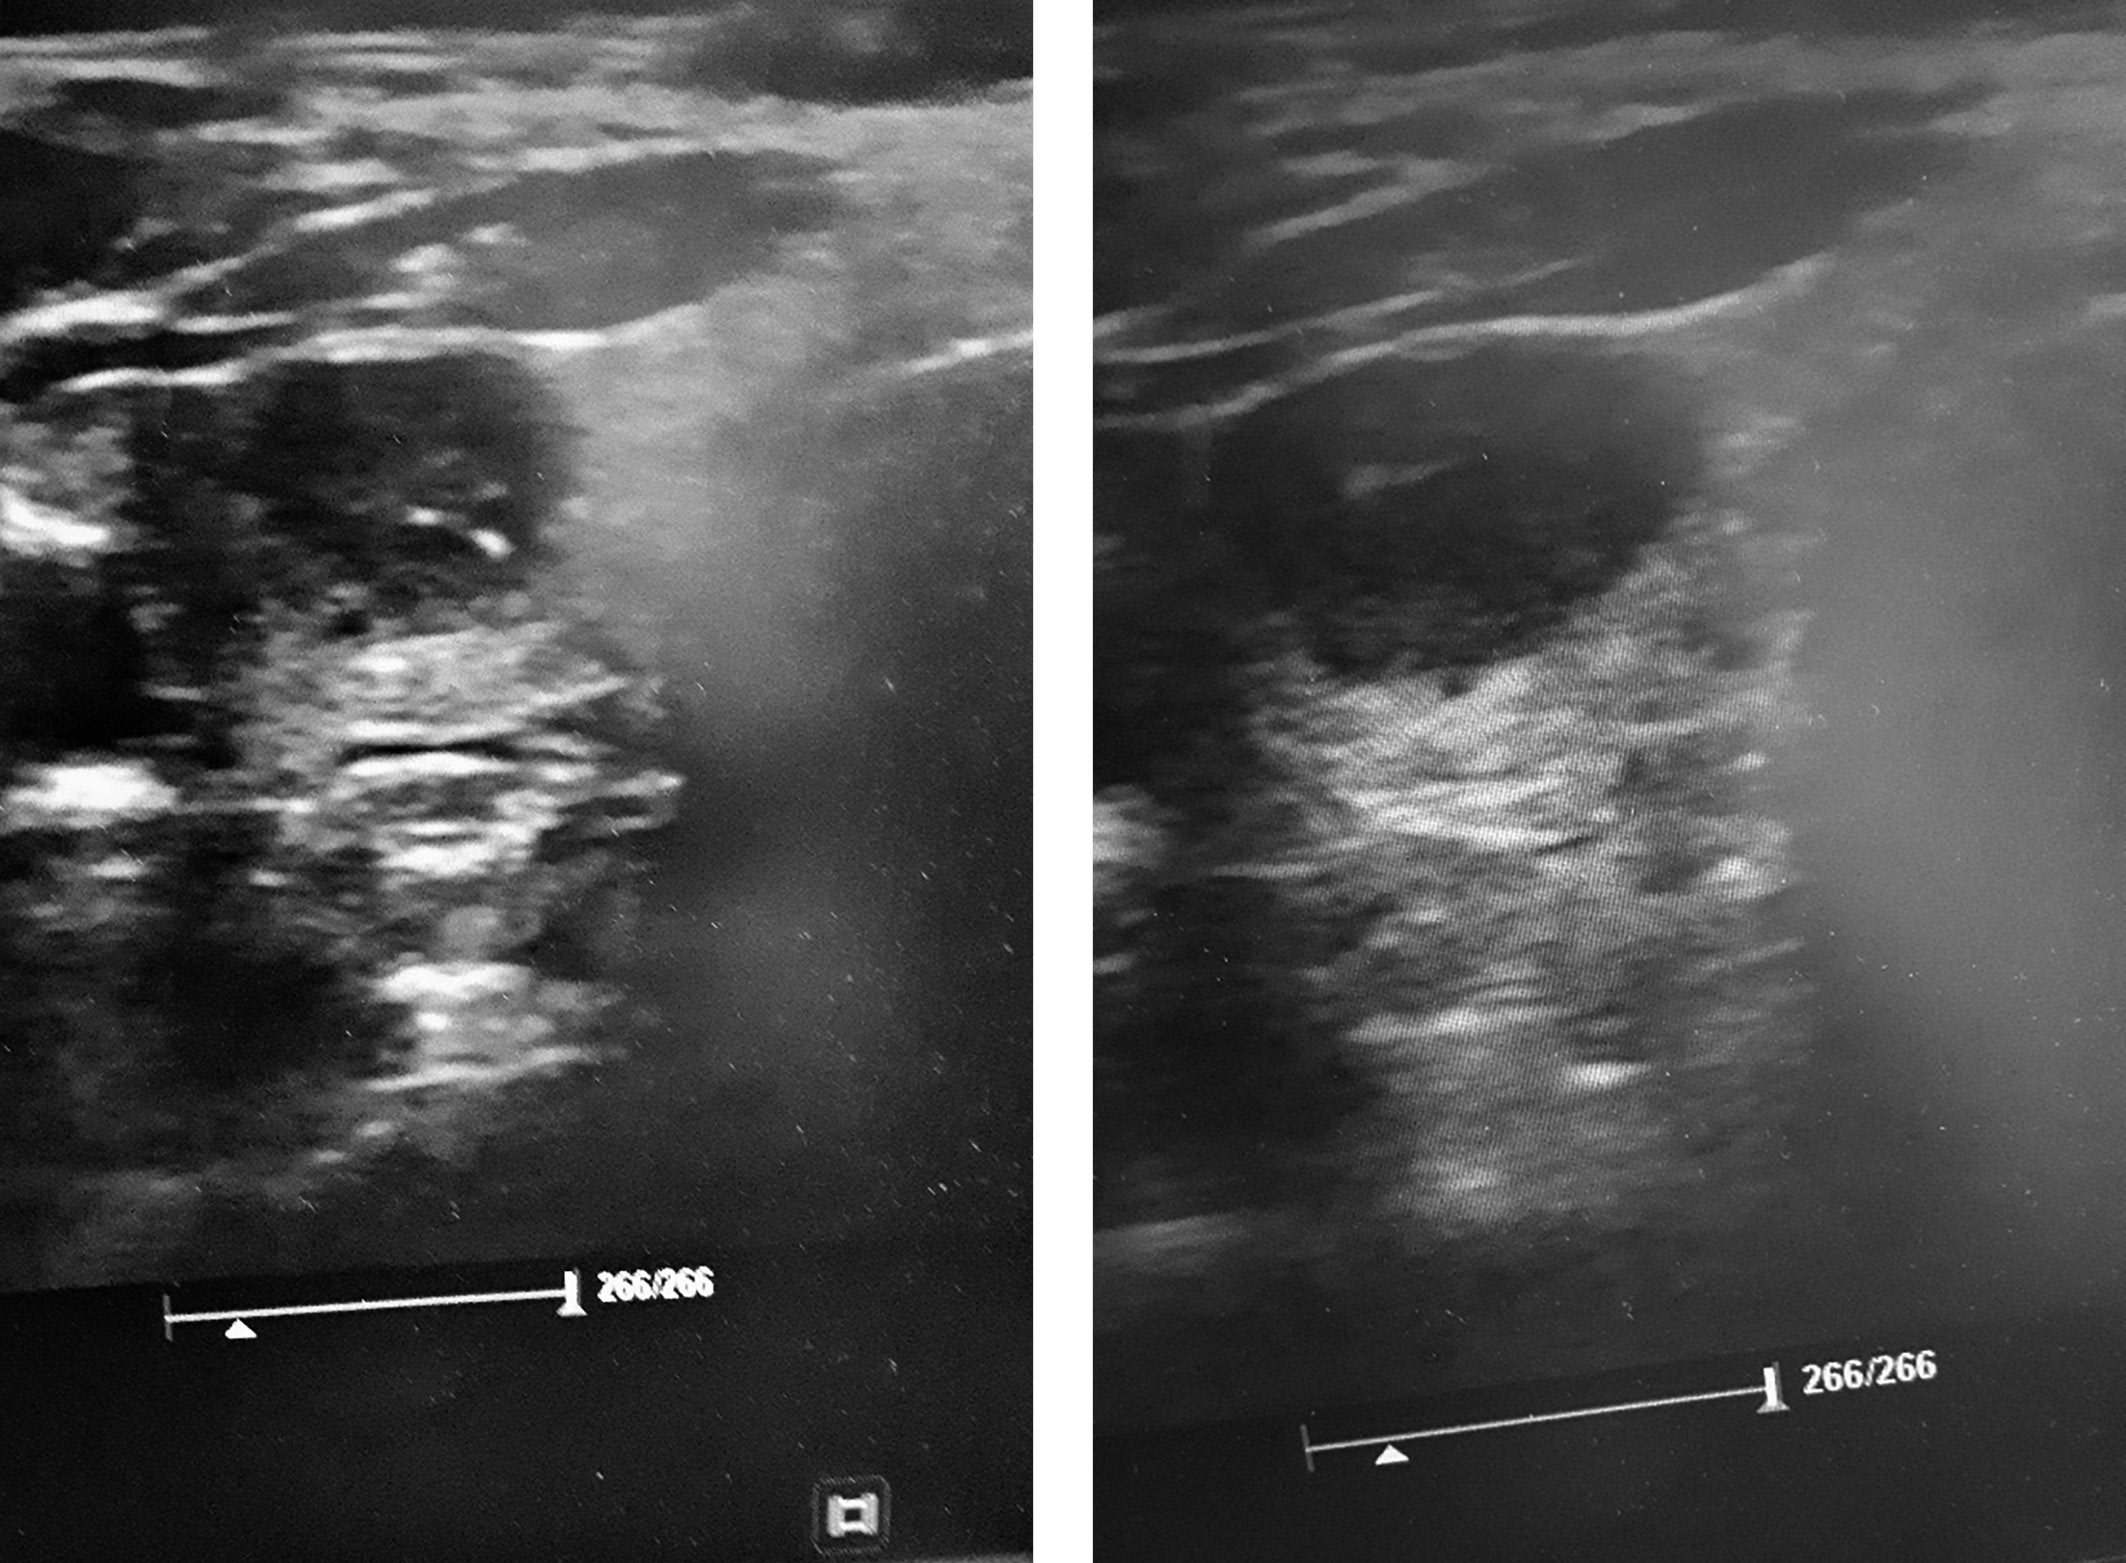

1. Рис. 1. Ультразвуковая картина медуллярного рака щитовидной железы пациентки Ш. (гипоэхогенность, неровные, нечеткие контуры, микрокальцинаты (TIRADS-5)). | |